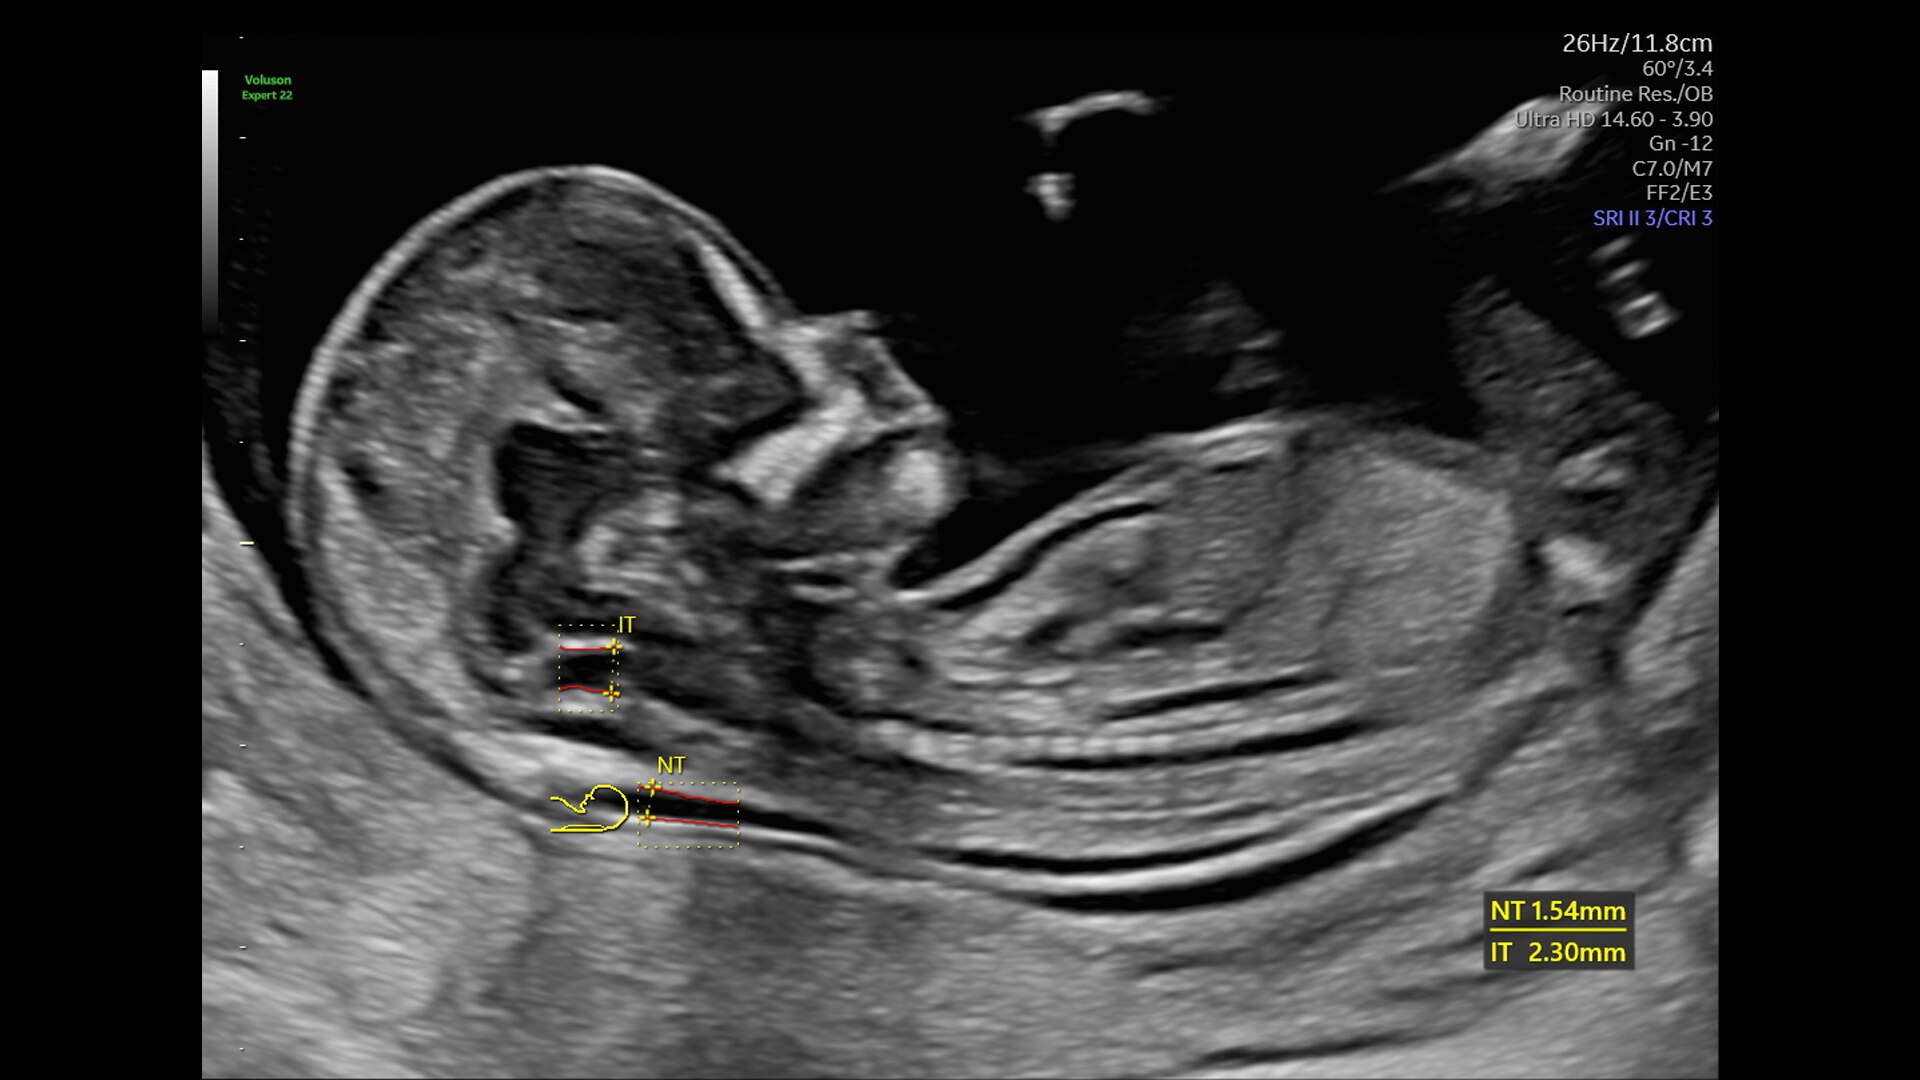

Complex cases come with enough uncertainty. That's why the Voluson Expert 22 is specifically designed for in-depth assessment of complicated anatomy — with pioneering first trimester, fetal cardiac, gynecological, and other pivotal technologies that focus on early detection and intervention.

First Trimester Exams

Perform detailed exams with high-resolution for early insights to fetal health